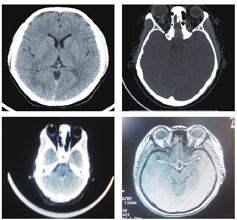

患者女,43岁。头痛3个月加重伴双眼胀痛、视力下降4天于2014年2月24日来我院眼科就诊。患者自述3个月前无明显诱因出现头颈部疼痛,呈跳痛,有时伴恶心,无呕吐,头痛发作前眼前无闪光、暗点等,亦无肢体麻木乏力感,无耳鸣、听力下降。于当地医院给予甘露醇治疗有效,但反复发作。入院眼部检查:双眼视力:0.8,双眼结膜无充血,角膜清亮,瞳孔直径约3 mm。对光反应稍迟钝,RAPD(+)晶状体透明,玻璃体清。双眼底:视乳头色淡红,边界不清,水肿隆起约2~3 D,视网膜静脉迂曲扩张,黄斑中心反光弥散,视网膜平伏(图1)。右眼压:12.5 mmHg,左眼压:11.0 mmHg。患者既往有冠心病史,于2010年在江西省人民医院行冠脉支架术。无糖尿病、高血压,无外伤等病史。血常规检查:血小板计数:580×109。脑脊液压力:250 mm H2O(正常120~180),显微镜及生化检查未见异常。眼底荧光素钠血管造影示:双眼视盘水肿(图2)。颅脑MRI、MRV、CT、眼眶CT均未见明显异常(图3)。全脑血管造影(CTA)示:考虑右侧横窦、乙状窦静脉血栓形成可能性大(图4)。明确诊断为:颅内静脉窦血栓形成,特发性血小板增多症,冠心病。